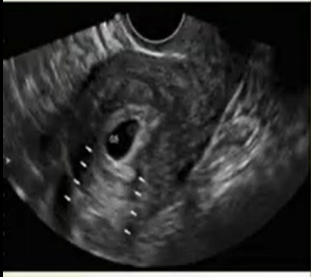

Posterior Acoustic Enhancement is an artifact that provides information regarding the cystic nature of the structure. As the sound beam travels through the body, it is attenuated at different levels dependent on the structure through which it is traveling. The attenuation rate is determined by the level of stiffness and density of the structure. Whereas shadowing is caused by the great level of attenuation of high level of stiffness and density in bone, a structure that is cystic allows the sound beam to travel through with less attenuation than the soft tissue that surrounds it which results in the area directly posterior to the structure to be brighter than the adjacent soft tissue. This allows the imager to differentiate between structures as being soft tissue masses or cystic (fluid-filled). Certain masses can appear to be cystic due to their hypoechoic or almost anechoic (black) appearance, however, without demonstrating posterior acoustic enhancement (brightness or white appearance directly posterior), it can be determined that they are not fluid-filled because of the attenuation that has traveled through the structure is the same as the adjacent soft tissue. However, a structure with the same appearance as a soft tissue mass can be determined to be cystic or have significant cystic components as it demonstrates posterior acoustic enhancement or brightness posterior to the structure.